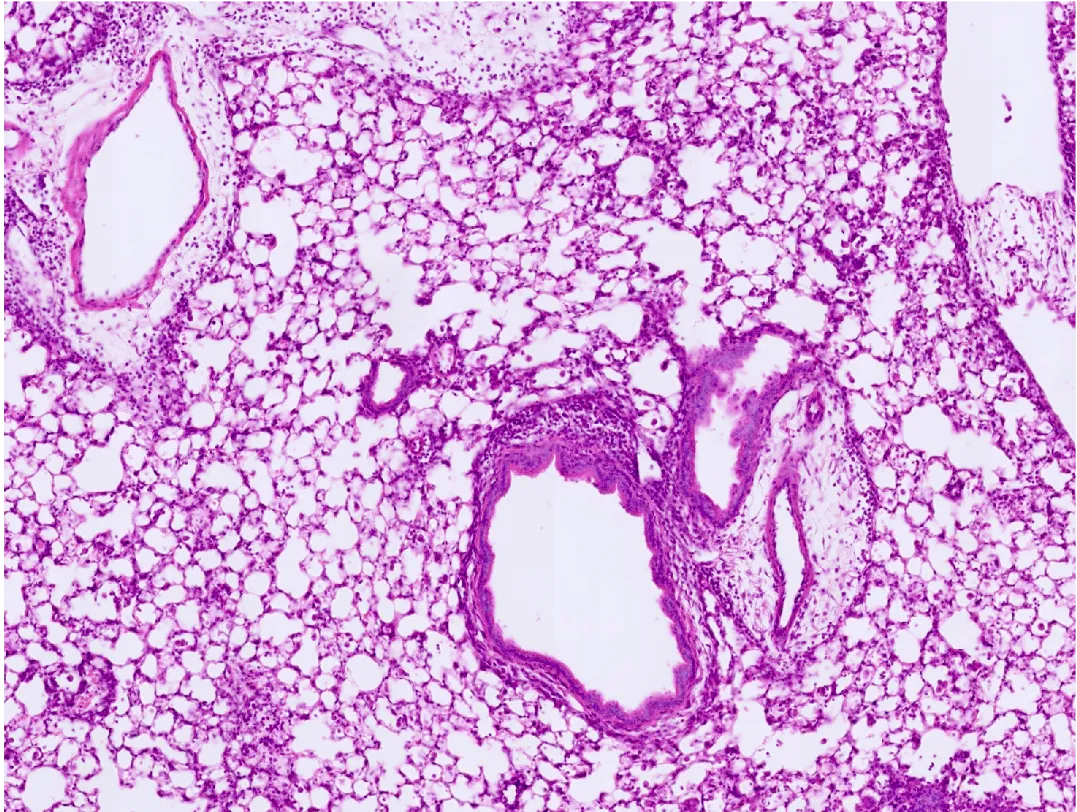

Histology image of inflamed lung tissue

Histology image of inflamed mouse lung tissue